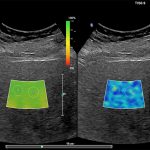

Imagini clinice:

Aplicatii: